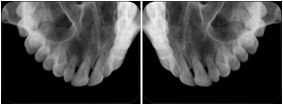

3. A patient in rural Minnesota experiences sudden vision loss and goes to a general ophthalmologist, who acquires OCT images and forwards them electronically along with a Structured Display to a retina specialist six travel hours away. The retina specialist is able to view the images in the standard layout that he is comfortable with, and to confirm that the patient has a choroidal neovascular membrane. He determines that is would be worthwhile for the patient to travel for treatment.

OCT Retinal Study with Cross Section and Navigation Structured Display

Figure OO-4. OCT Retinal Study with Cross Section and Navigation Structured Display